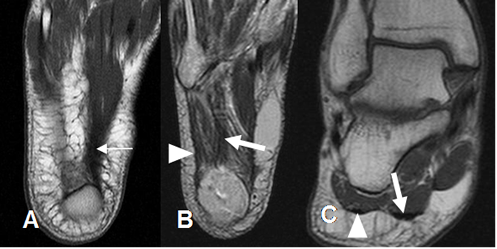

Fig 19. Fascia plantar normal.

A y B: RM axial en T1 y C: RM coronal en T1. Rama medial (Flecha delgada), central (Flecha gruesa) y lateral (Cabeza flecha).

Fig 20. Fascia plantar normal.

A: RM sagital en T2 y B: RM sagital en STIR. Estructura hipointensa en todas las secuencias.